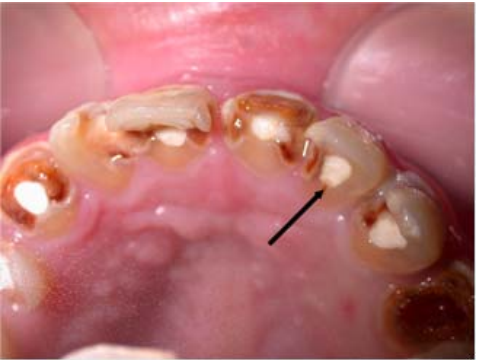

54.下圖中箭頭所指的部位的牙融合(fusion),是那些牙齒的融合?

(A)42與43 (B)41與42 (C)81與82 (D)82與83